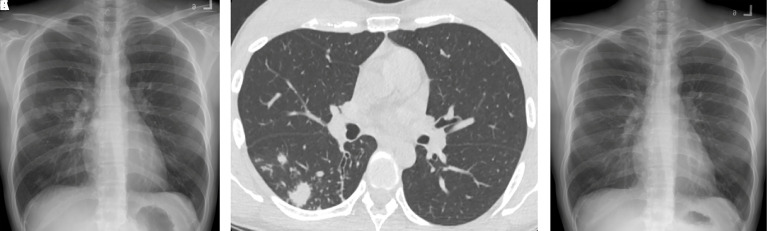

Results: Out of the 106 individuals identified with subclinical pulmonary TB, 84 met the criteria for inclusion in the analysis. The study found lower radiographic extent and increasing age were key attributes of culture-negative subclinical pulmonary TB. The odds ratios (95% confidence interval) were 7.18 (1.76 to 29.35) and 1.07 (1.01 to 1.13), respectively. They tend to have lower rates of bilateral involvement in both chest x-ray (8.5% vs. 32.0%, p=0.006) and computed tomography (15.4% vs. 42.9%, p=0.035). However, no other specific radiographic findings were identified.

Conclusions: People with culture-negative subclinical pulmonary TB were likely to have less radiographic -severity, reflecting early disease. Nevertheless, no radiographic patterns, except for unilaterality, were related to culture-negative subclinical pulmonary TB.